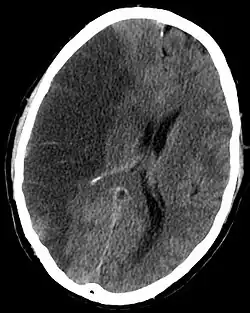

Tomografia mostrando uma área enegrecida compatível com AVC isquêmico

Os acidentes vasculares do cérebro podem ser basicamente decorrentes da obstrução de uma artéria que irriga o cérebro (ou seja, por isquemia) ou podem ser por vazamento de sangue de um vaso sanguíneo (ou seja, hemorrágico).